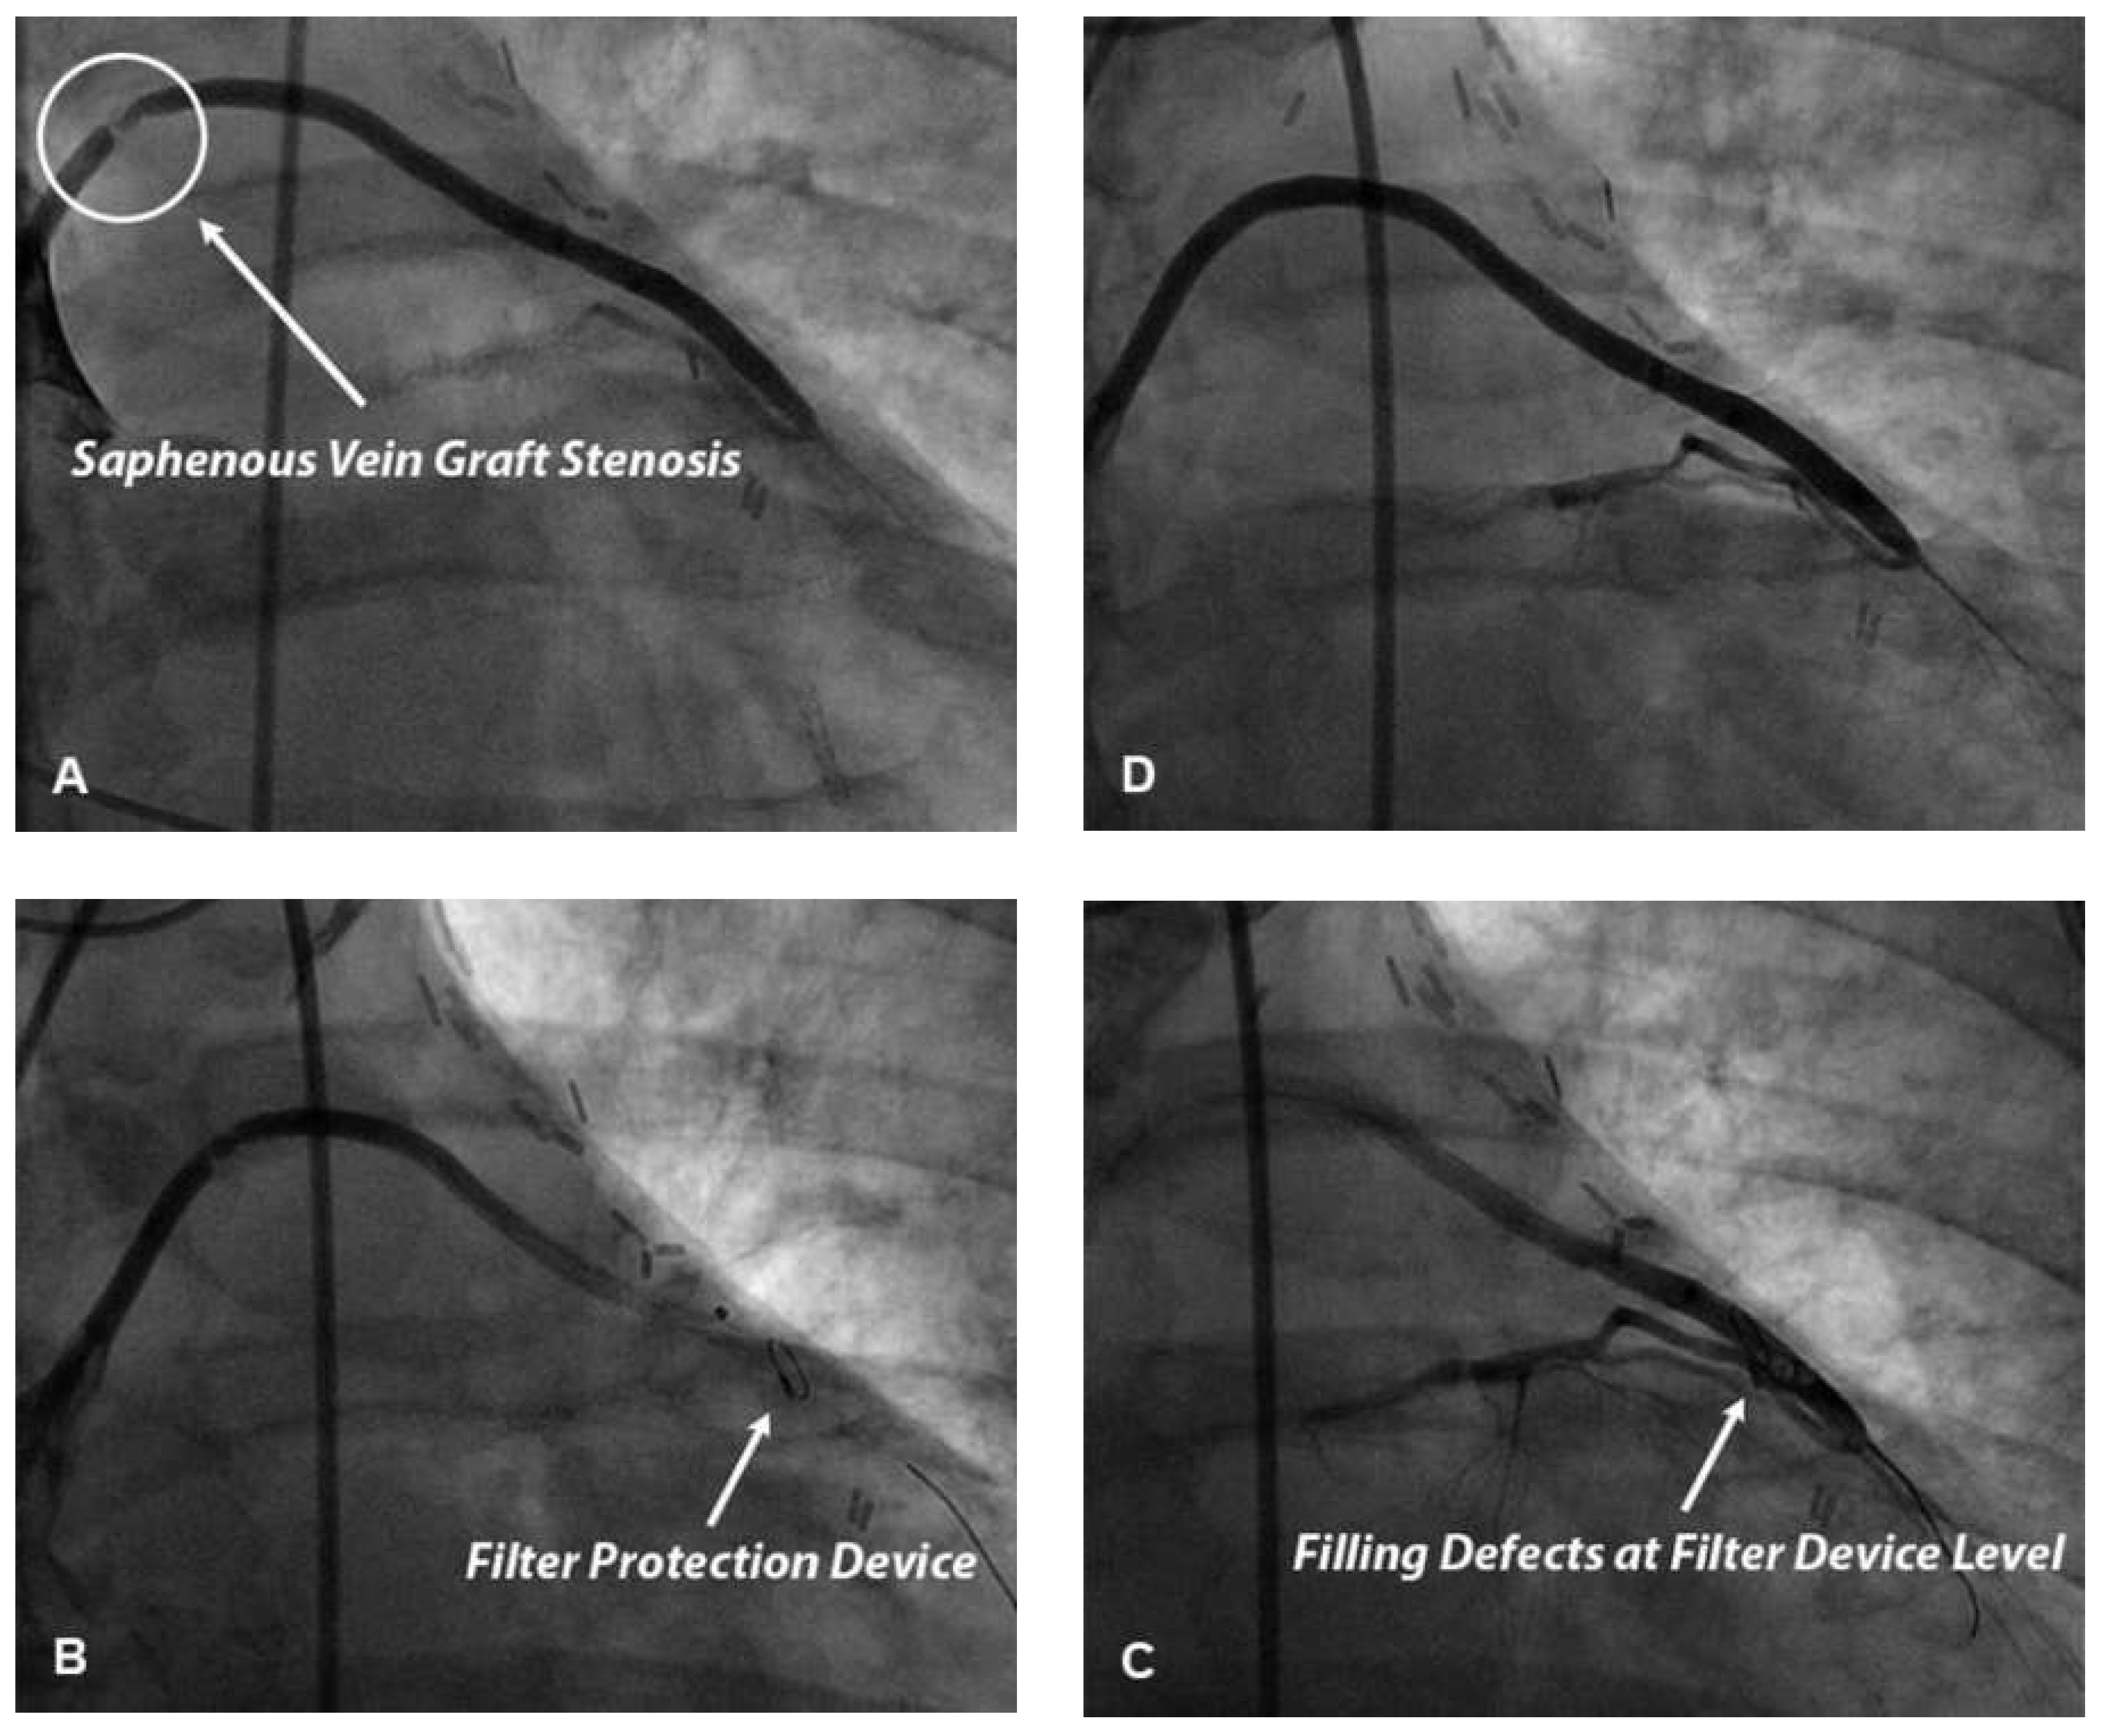

Figure 3. Panel A. Coronary angiography of a 74-year-old smoking, hypertensive, dyslipidemic and diabetic patient presenting with typical stable angina and undergone saphenous vein coronary artery bypass graft 10 years ago. Angiography shows an 85% stenosis in the proximal portion of the saphenous vein graft for the first diagonal artery. Panel B. Lesion was crossed with a non-deployed filter device positioned over a guide-wire. Filter device was then deployed into the distal portion of the graft. Panels C and D. Balloon angioplasty followed by drug-eluting stent implantation was subsequently performed. Contrast medium filling defects were detected suggesting the presence of embolized material in the basket of filter device. After filter device retrieval good final angiographic result with a post-percutaneous coronary intervention TIMI 3.

Distal protection devices used in the setting of PCI essentially consist of a filter device placed between the target lesion and the distal vasculature (Figure 2). Filter-based distal protection devices allow blood flow during PCI and prevent distal migration of microparticles whose diameter is greater than pore size (usually 100–150 μm). Distal protection devices have not been shown to reduce no-reflow occurrence and improve prognosis in STEMI patients treated with pPCI in two large scale clinical trials, the EMERALD trial and the DEDICATION trial [44,45]. Therefore they have a class III recommendation in 2012 ESC guidelines in this setting [39].

The use of filter distal protection devices has been demonstrated to reduce the occurrence of both no-reflow and periprocedural myocardial infarction in elective PCI performed in saphenous vein grafts (Figure 3) [46]. Distal embolisation during elective PCI in saphenous vein grafts, as opposed to native coronary arteries, is more likely to be due to large necrotic and/or lipid emboli essentially originating from vessel wall plaque. Differences in amount and/or composition of embolised material could explain, at least in part, differences in results of clinical trials investigating the use of distal protection devices in pPCI and elective saphenous vein graft PCI. In this setting distal balloon occlusion devices and proximal occlusion devices seem to be as effective as filter devices in preventing both no-reflow and periprocedural myocardial infarction and, therefore, represent a valid alternative to a filter device [47,48].